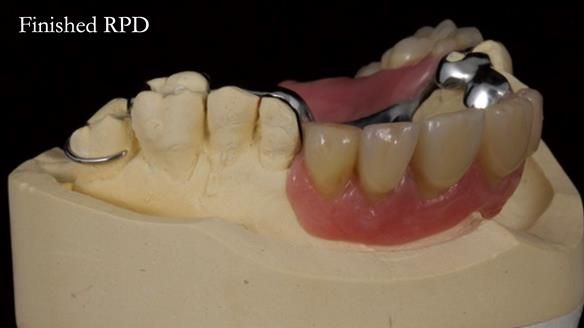

Keith’s case was one of the most challenging and rewarding cases I’ve treated this year. This 64 year old man presented with ill-fitting acrylic partial dentures that lacked stability, retention, and aesthetics. They constantly broke. He had lost the upper front teeth in a road traffic accident in his early 20s. The unopposed teeth had erupted, taking up space. After careful planning, we made a durable, metal-based upper partial denture/splint to address his dental concerns. He loved the outcome.

1. Denture design: A custom cobalt-chromium framework was Scandinavian-designed to maximise stability, protect the remaining teeth, and allow for future additions if needed.

2. Onlay preparations: Composite onlays were fitted for his upper left premolars to repair these teeth and support the new denture.

Keith’s denture incorporated a Duracetal shell clasp on upper right first premolar (Myerson), which are designed to be virtually visible, providing a more aesthetic solution while enhancing patient comfort. The Scandinavian-inspired approach, based in modern removable prosthodontic techniques, ensured the denture was not only durable but also visually pleasing. Additionally, the design was carefully planned to allow for future modifications, ensuring that if Keith loses additional teeth, the denture can be adapted rather than replaced entirely.

I also used the Dahl concept to re-establish the occlusion upon fitting the RPD, which helped to intrude the lower left canine without needing to grind it too much.